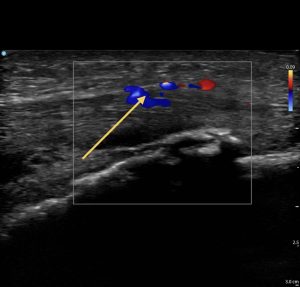

エコー上 :膝蓋腱表層に低エコー像+、ドプラー+

徒手検査とエコー画像検査を行ない膝蓋腱損傷と判断 しました。